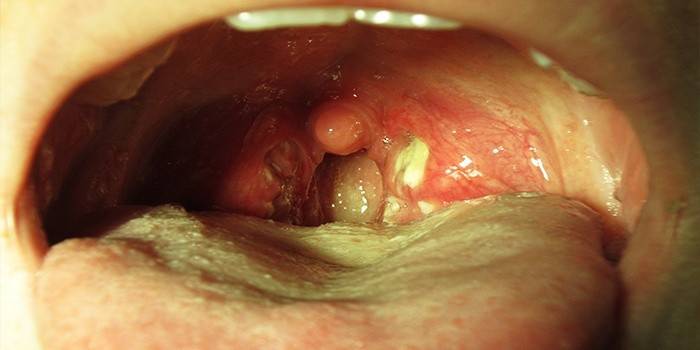

• збільшення, запалення мигдалин, труднощі з ковтанням;

• поява гнійного нальоту на мигдаликах;